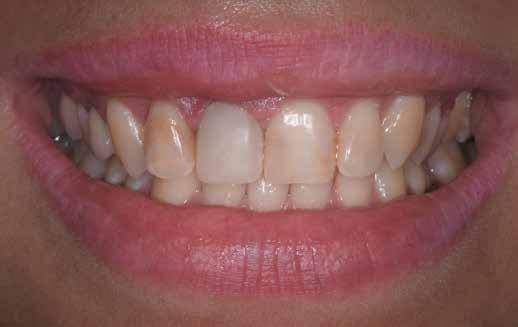

A 2020 januárjában elkezdett kezeléssorozat befejezését az év márciusában, hazánkba is begyűrűző Covid-19 pandémia késleltette, így kb. 6 hónap gyógyulás után láttunk hozzá az emergencia profil és a gingivális zenit ideiglenes koronával történő formázásához (11. és 12. kép). A 3 hetente végzett apró alakításokkal sikerült megfelelő ínyprofilt kialakítani, a „rózsaszín esztétika” a páciens számára is megfelelő volt. A bal felső nagymetsző fog meziális kompozit tömés cseréjét követően, individualizált nyitott kanalas lenyomati fejet készítettünk: az akrilát ideiglenes korona profilját átlátszó szilikonnal lemásoltuk, majd a körszimmetrikus gyári lenyomati fej és az ideiglenes korona kontúrja közötti hézagot folyékony kompozittal töltöttük ki (13. kép). Az így készített egyéni lenyomati fejjel vettünk lenyomatot a végleges, kerámialeplezésű cirkónium-dioxid vázas, átmenő csavaros rögzítésű koronához. (A fogtechnikai munkát Nébl Péter fogtechnikusmester készítette.), (14., 15., 16 és 17. képek).

A kész korona átadásakor a páciens elégedett volt az esztétikával, az azóta eltelt évben rendszeres kontrollokon jelent meg, melyek során meggyőződtünk a kemény- és lágyszövetek stabilitásáról (18. és 19. képek).

17. a–b képek: A kész munka átadáskor. 18. a–c képek: 1 éves kontroll. 19. kép: Intraorális kontroll röntgen felvétele 1 évvel az átadás után.